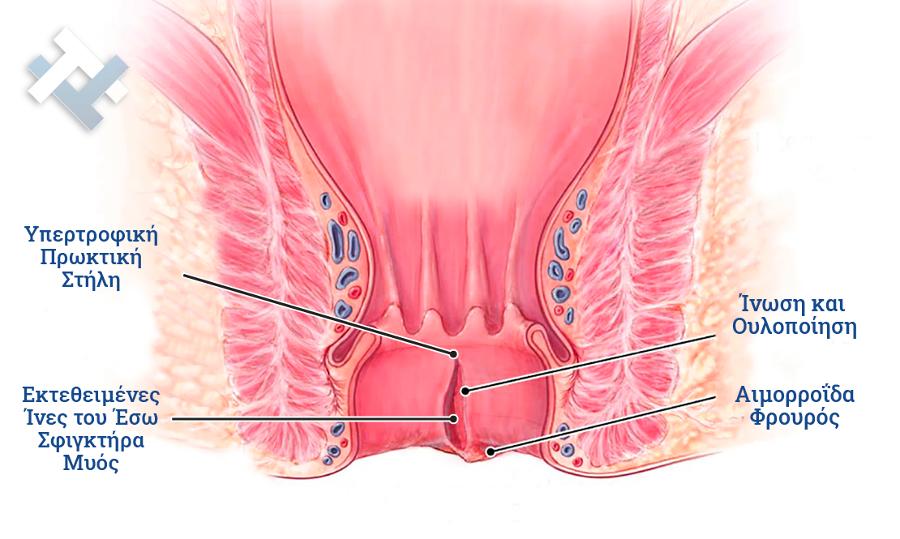

Ο Γενικός Χειρουργός Λιάγκος Γεώργιος MD PhD εκτελεί τις επεμβάσεις Λαπαροσκοπικά, Ενδοσκοπικά, Ανοιχτά Ελάχιστα Επεμβατικά και με Laser. Η θεραπεία εξατομικεύεται σε κάθε ασθενή ανάλογα με τις ανάγκες του. Αναλαμβάνει περιπτώσεις όπως κήλες και κοιλιοκήλες (αντιμετώπιση βουβωνοκήλης, αντιμετώπιση ομφαλοκήλης, θεραπεία επιγαστρικής κήλης, κήλη των αθλητών (Σύνδρομο κοιλιακών προσαγωγών), αντιμετώπιση μετεγχειρητικής κήλης, θεραπεία Μηροκήλης), πέτρες στη χοληδόχο κύστη, λαπαροσκοπική χολοκυστεκτομή, αντιμετώπιση Κύστη Κόκκυγος με λέιζερ (laser), παθήσεις πρωκτού, χειρουργική laser σύγχρονων κυκλικών ινών (αιμορροΐδες αντιμετώπιση, θεραπεία αιμορροϊδων με laser (LHP), αφαίρεση αιμορροΐδων με υπερήχους (HALL-RAR), χωρίς Χειρουργείο με ελαστικούς δακτυλίους (Τεχνική BARON-RBL), θεραπεία ραγάδας πρωκτού (Ραγάδα δακτυλίου), θεραπεία περιεδρικού συριγγίου, θεραπεία περιεδρικού αποστήματος, κονδυλώματα πρωκτού Θεραπεία, δερματικό ράκος (Skin tag) εκτομή, αντιμετώπιση Kνησμού, καρκίνος πρωκτού θεραπεία), παθήσεις Δέρματος, χειρουργική με laser CO2, αφαίρεση μορφωμάτων δέρματος - βιοψίες, αφαίρεση ελιάς (Σπίλου), σμηγματογόνος κύστης θεραπεία, αφαίρεση λιπώματος, είσφρυση όνυχος χειρουργείο, καρκίνος δέρματος θεραπεία, οξεία σκωληκοειδίτιδα, παθήσεις Λεπτού και Παχέος Εντέρου, ειλεός λεπτού εντέρου, εκκολπωμάτωση (Εκκολπωματίτιδα) σιγμοειδούς, καρκίνος παχέος εντέου, κολοστομίες, port χημειοθεραπείας κ.α.

Ο Γενικός Χειρουργός Λιάγκος Γεώργιος MD PhD εκτελεί τις επεμβάσεις Λαπαροσκοπικά, Ενδοσκοπικά, Ανοιχτά Ελάχιστα Επεμβατικά και με Laser. Η θεραπεία εξατομικεύεται σε κάθε ασθενή ανάλογα με τις ανάγκες του. Αναλαμβάνει περιπτώσεις όπως κήλες και κοιλιοκήλες (αντιμετώπιση βουβωνοκήλης, αντιμετώπιση ομφαλοκήλης, θεραπεία επιγαστρικής κήλης, κήλη των αθλητών (Σύνδρομο κοιλιακών προσαγωγών), αντιμετώπιση μετεγχειρητικής κήλης, θεραπεία Μηροκήλης), πέτρες στη χοληδόχο κύστη, λαπαροσκοπική χολοκυστεκτομή, αντιμετώπιση Κύστη Κόκκυγος με λέιζερ (laser), παθήσεις πρωκτού, χειρουργική laser σύγχρονων κυκλικών ινών (αιμορροΐδες αντιμετώπιση, θεραπεία αιμορροϊδων με laser (LHP), αφαίρεση αιμορροΐδων με υπερήχους (HALL-RAR), χωρίς Χειρουργείο με ελαστικούς δακτυλίους (Τεχνική BARON-RBL), θεραπεία ραγάδας πρωκτού (Ραγάδα δακτυλίου), θεραπεία περιεδρικού συριγγίου, θεραπεία περιεδρικού αποστήματος, κονδυλώματα πρωκτού Θεραπεία, δερματικό ράκος (Skin tag) εκτομή, αντιμετώπιση Kνησμού, καρκίνος πρωκτού θεραπεία), παθήσεις Δέρματος, χειρουργική με laser CO2, αφαίρεση μορφωμάτων δέρματος - βιοψίες, αφαίρεση ελιάς (Σπίλου), σμηγματογόνος κύστης θεραπεία, αφαίρεση λιπώματος, είσφρυση όνυχος χειρουργείο, καρκίνος δέρματος θεραπεία, οξεία σκωληκοειδίτιδα, παθήσεις Λεπτού και Παχέος Εντέρου, ειλεός λεπτού εντέρου, εκκολπωμάτωση (Εκκολπωματίτιδα) σιγμοειδούς, καρκίνος παχέος εντέου, κολοστομίες, port χημειοθεραπείας κ.α.